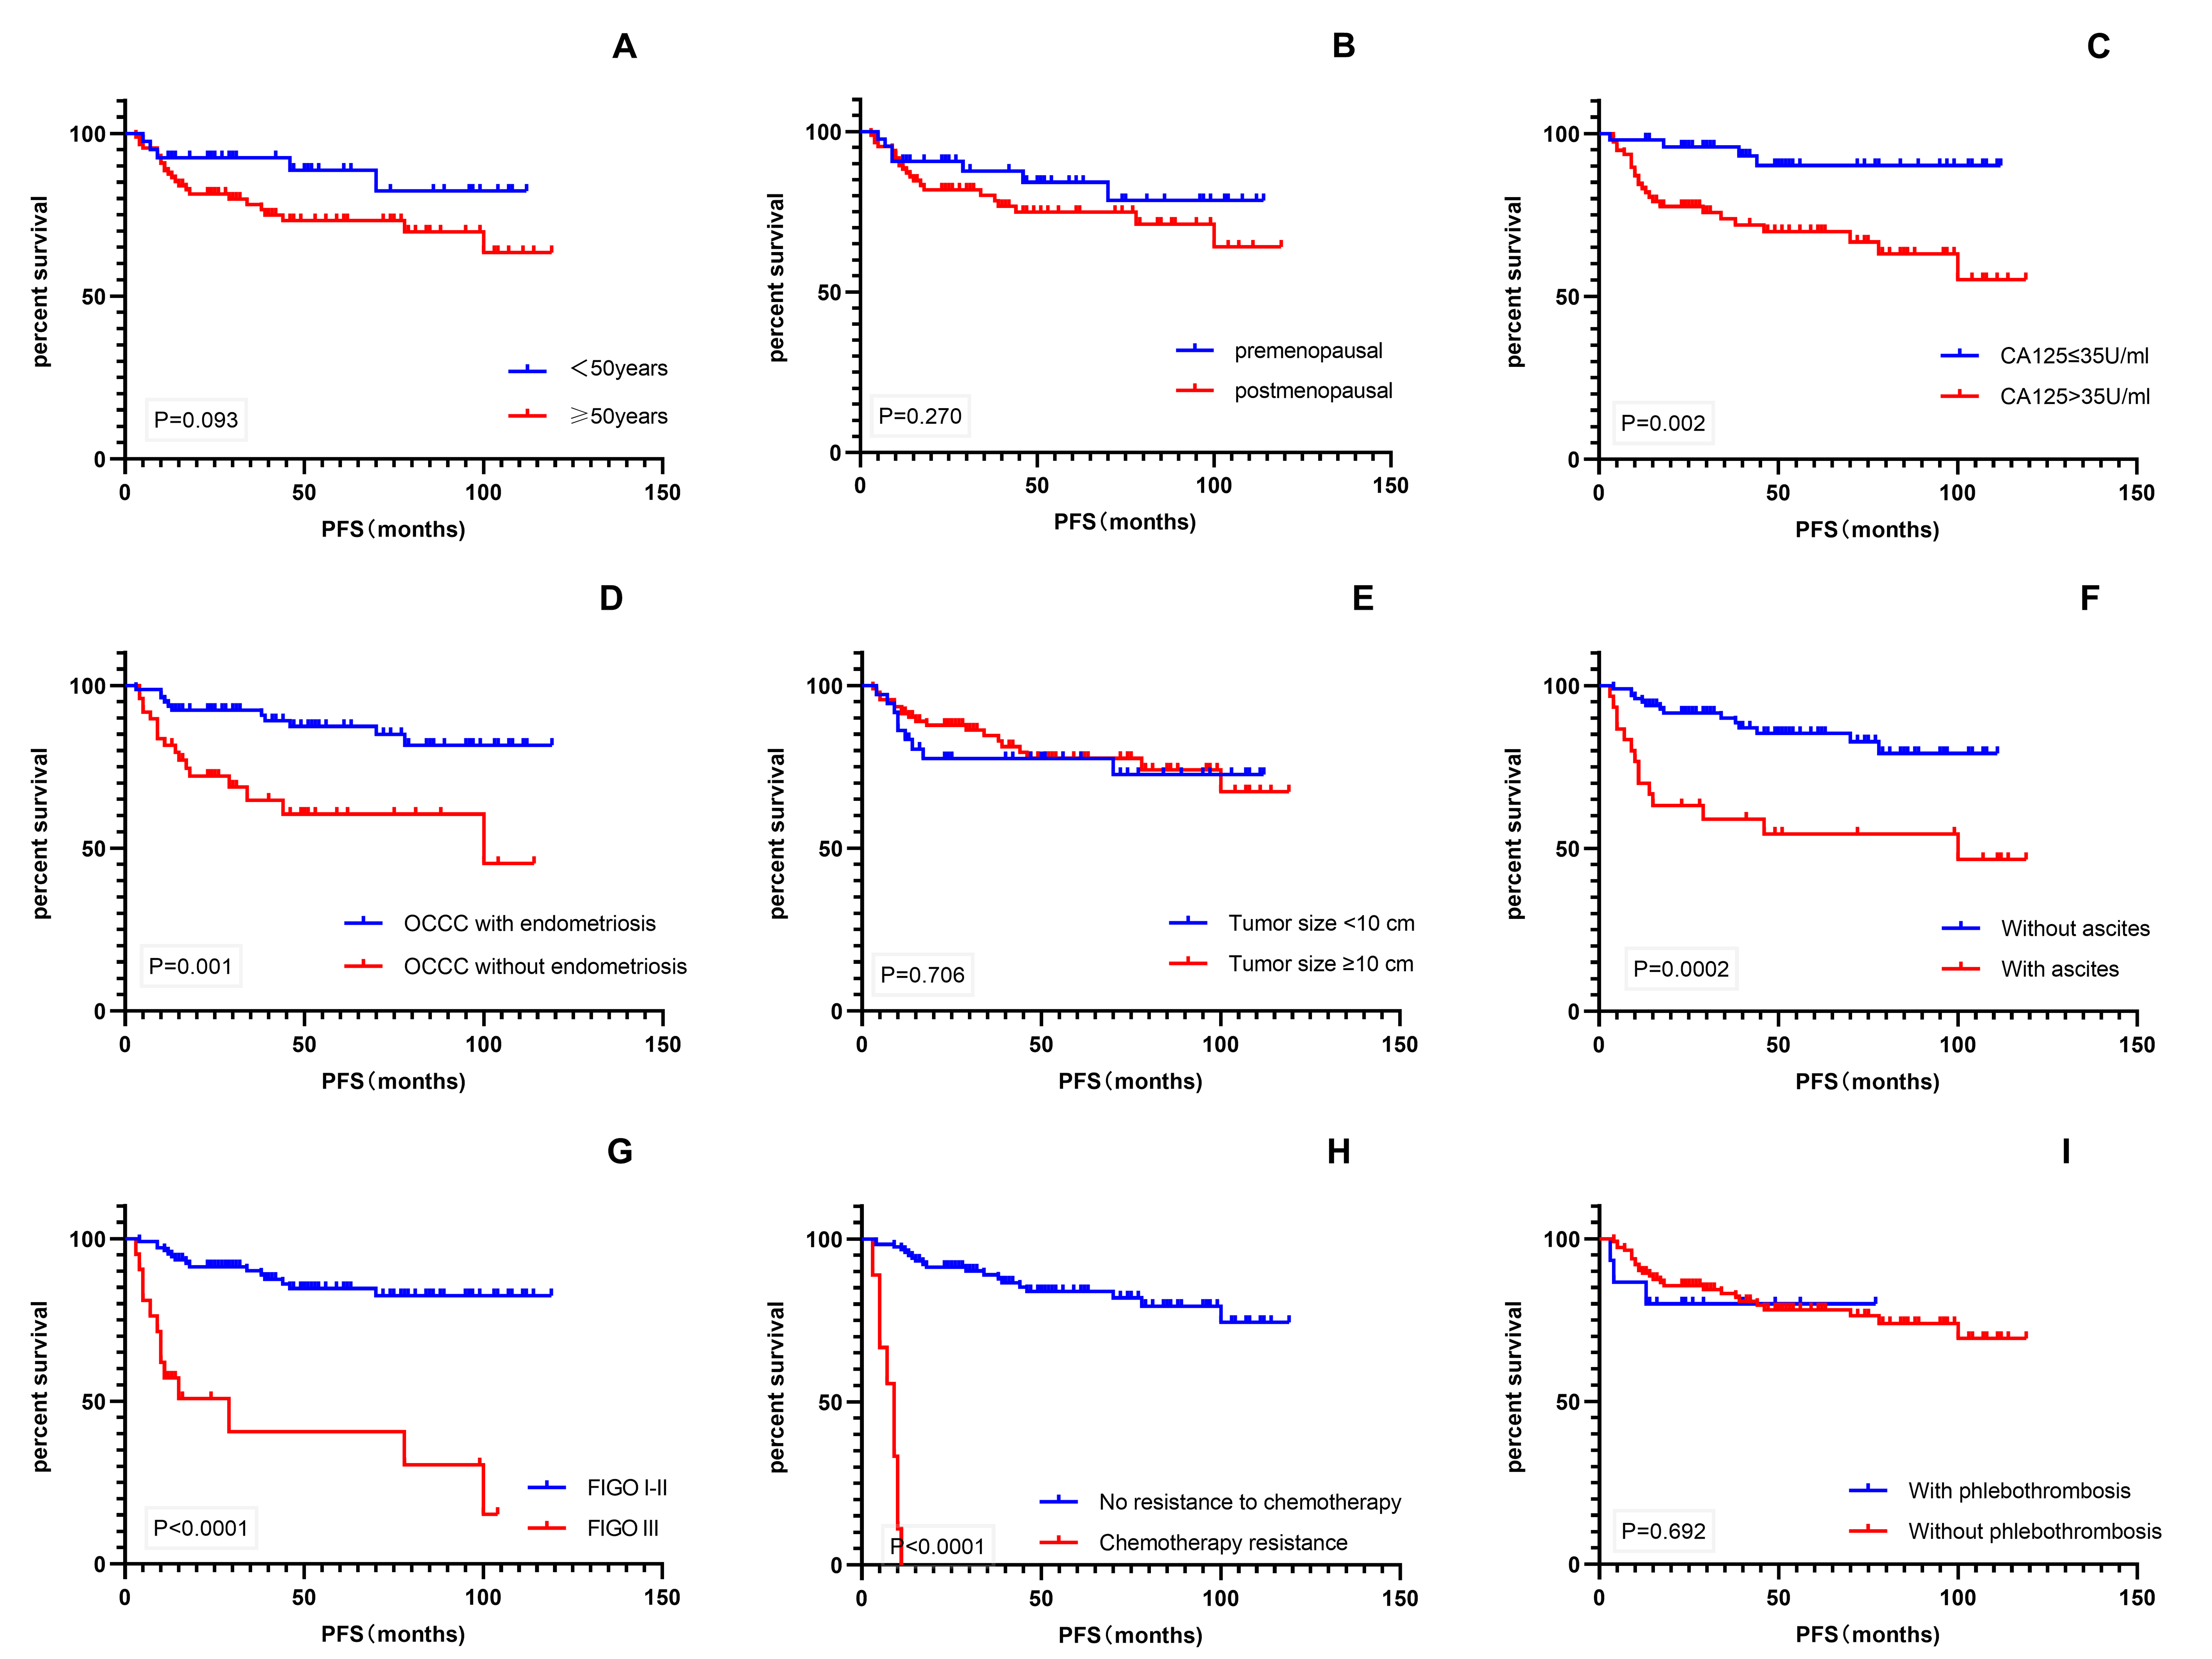

Kaplan–Meier univariate analysis using survival time as the dependent variable

was performed for various factors that might affect patient prognosis (Fig. 4).

The results showed that CA-125 level, endometriosis, ascites, FIGO stage, and

chemotherapy resistance were significant prognostic factors for PFS (p

Fig. 4.

Fig. 4.Kaplan–Meier survival curves. (A–I) PFS of patients with age, menopausal status, CA-125 level, endometriosis, tumor size, ascites, FIGO stage, chemotherapy resistance, and phlebothrombosis. PFS, progression-free survival; CA-125, cancer antigen 125; FIGO, International Federation of Gynecology and Obstetrics.